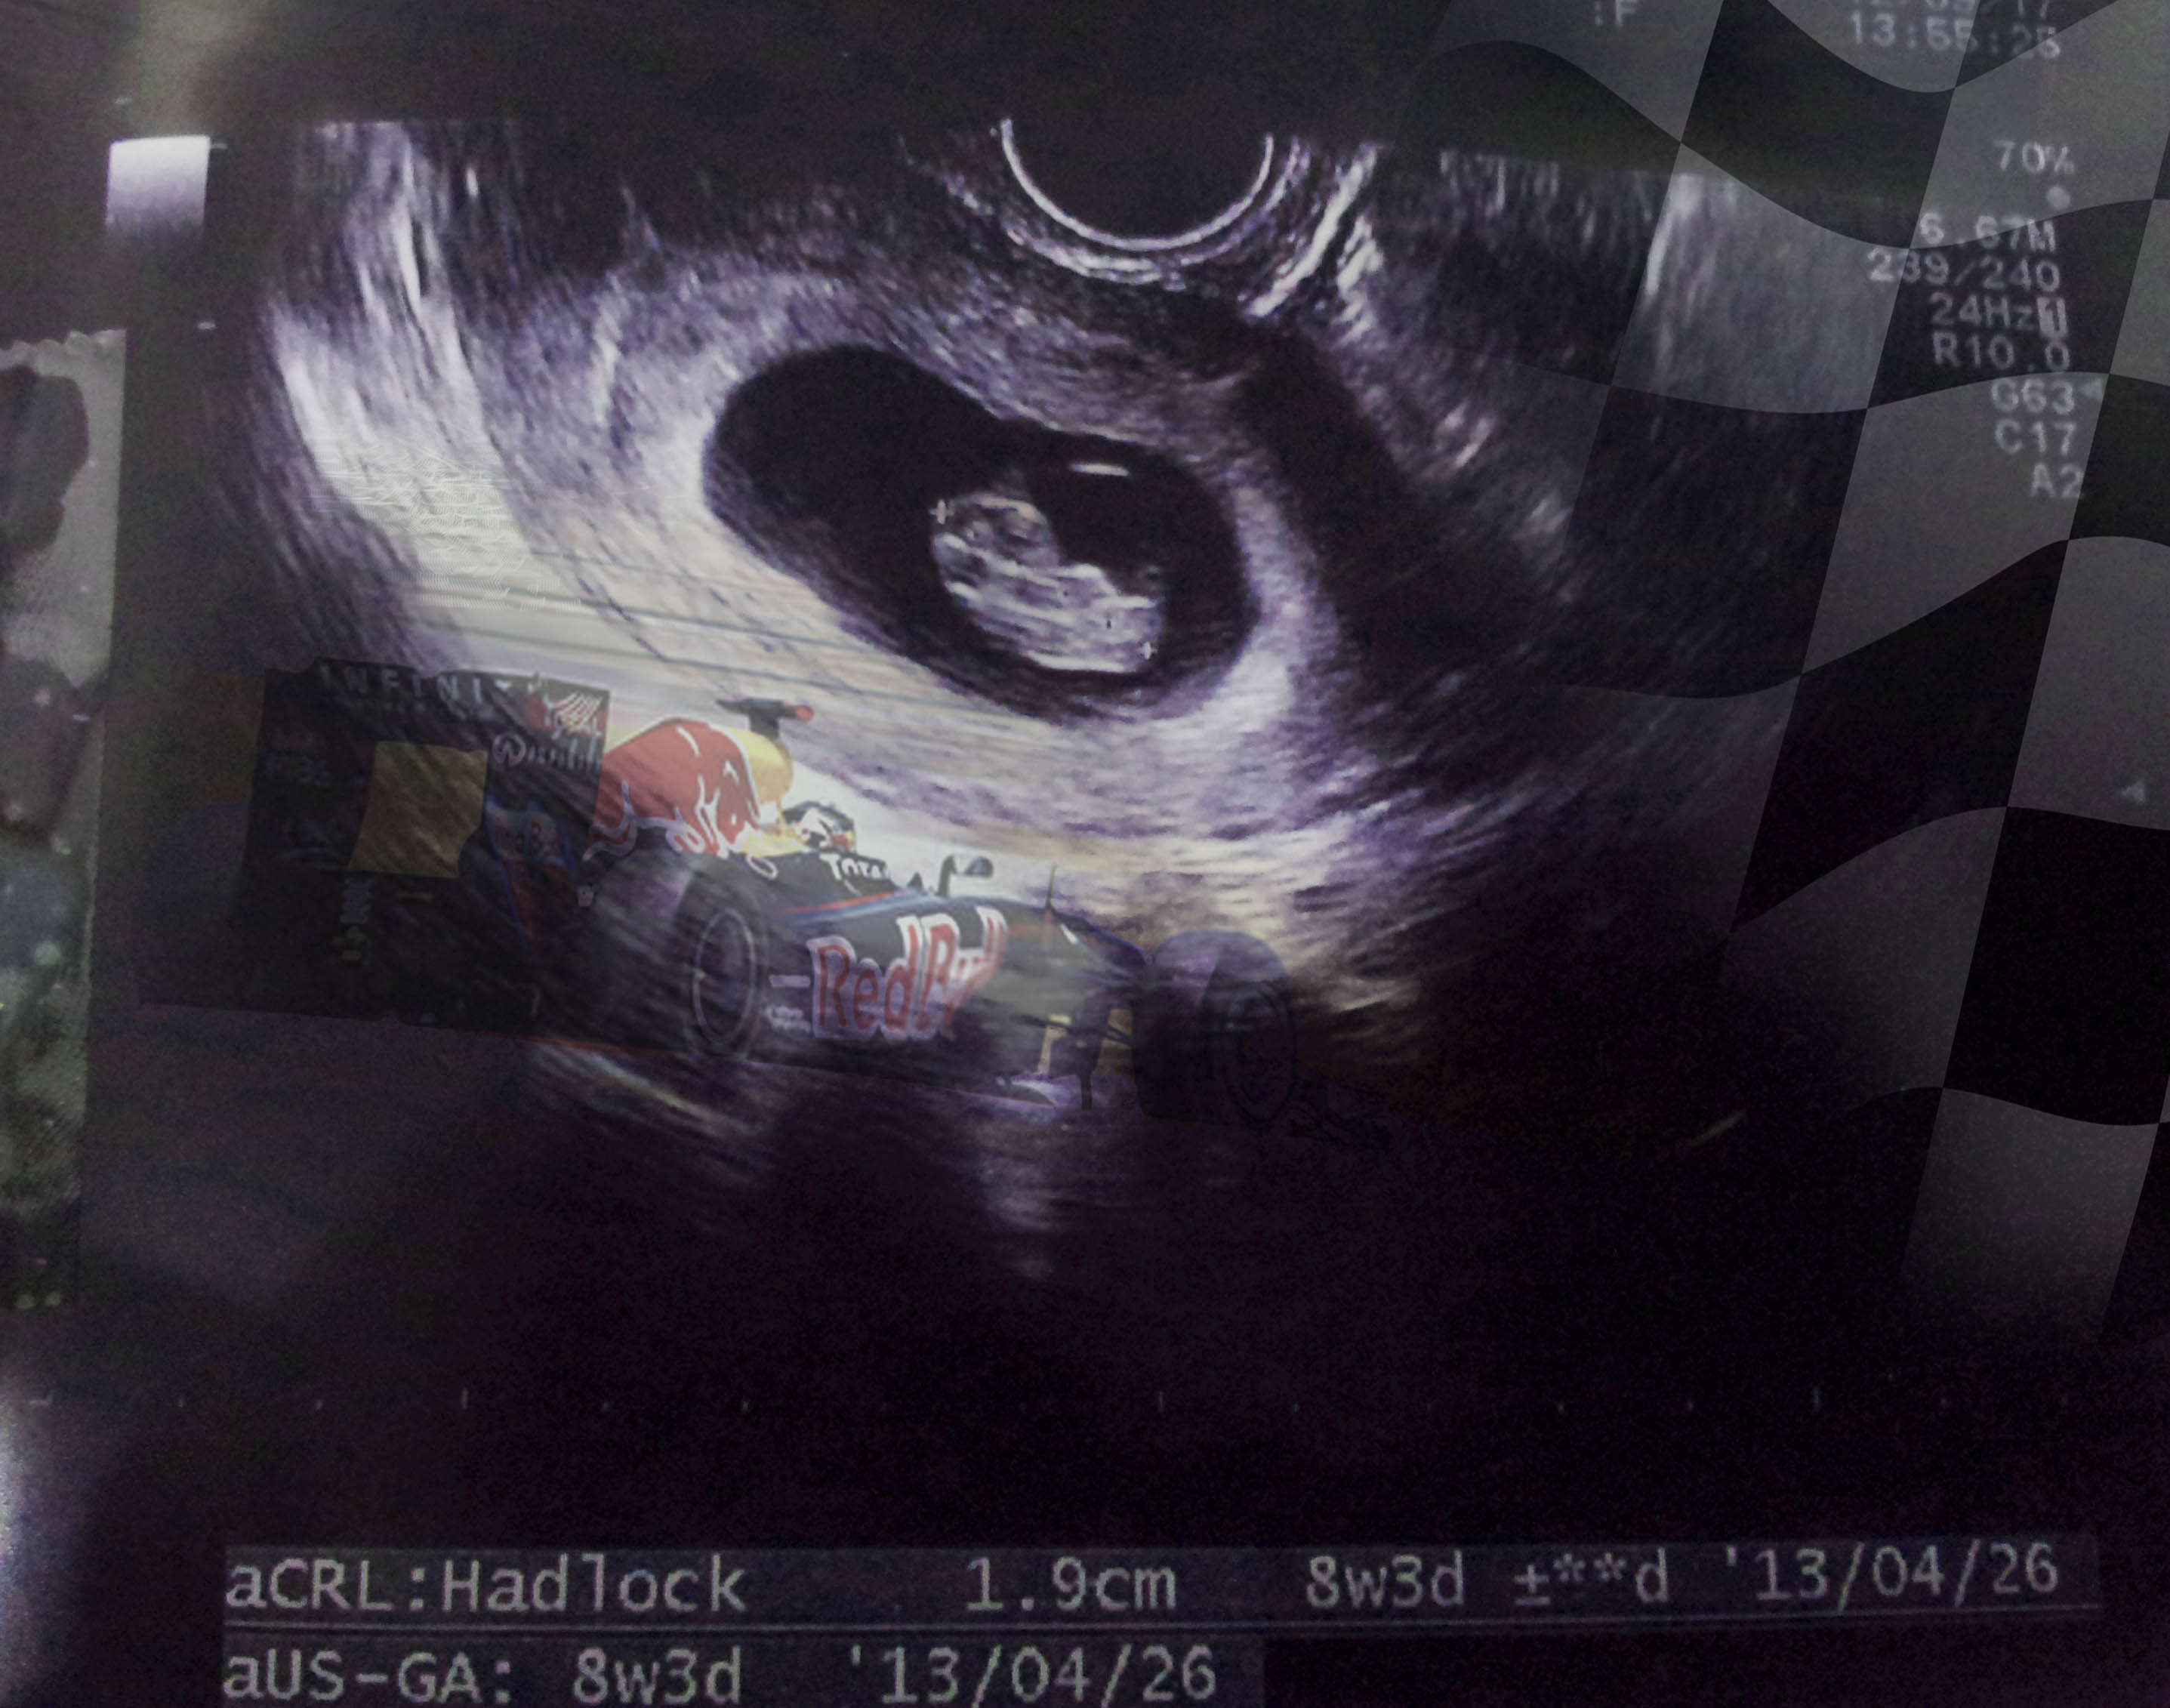

Dear Lil — you are 1.9 centimeters long you are about to lose your tail and your heart is already lapping mine three times over.

This week was our final doc appointment in South Korea Lil. Week 7 and 8 were pretty busy times for you in there. You got some feets and hands and are about to lose that tail…sorry, but its less cool once you get out. You’re about 1.9 cm now and your super brain is now taking shape but thats not the only superness going on inside you.

Your heart, is now beating at a turbocharged 175 beats per minute. Now it took daddy some time to figure this out…. his heat beats at roughly 55bpm. Daddies heart puts out a relatively slow .91 beats ber second while you are crushin it at 20.61 thumps a tick. Now, if we change that into a very important stat….how fast you go from 0-60, you’ll learn more about this later….then it really gets cool. Daddy’s heart moves from 0-60bpm at a 50cc scooter speed of 65.9 seconds. You, on the other hand are spittin flames at 0-60bpm speed of 20.61 seconds.

You would lap me three times Lil! Needless to say, that kinda horsepower needs high octane juice so mom and I have been doing our best to give it to ya. You love your OJ, cucumbers and saltines best 🙂 Mom is also giving you lots of her energy to keep your motor running strong.